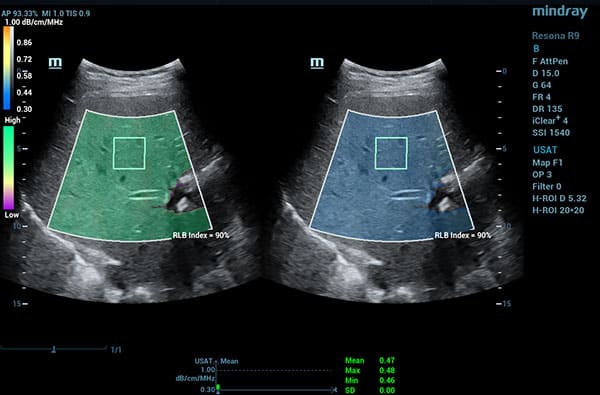

To address the changing needs of today’s value-based care environment, the Resona 7 Ultrasound System Platinum Edition was developed to capture clear, uniform images for radiology, vascular, women’s health, pediatric, and shared service imaging applications.

Premium imaging coupled with advanced workflow technologies help ease clinicians’ increasing workload by offering intuitive and easy-to-use smart tools and AI-enhanced technologies to elevate clinician and patient satisfaction. The user-directed ergonomic design is ideal for daily use, enabling clinicians to capture premium images without sacrificing comfort.